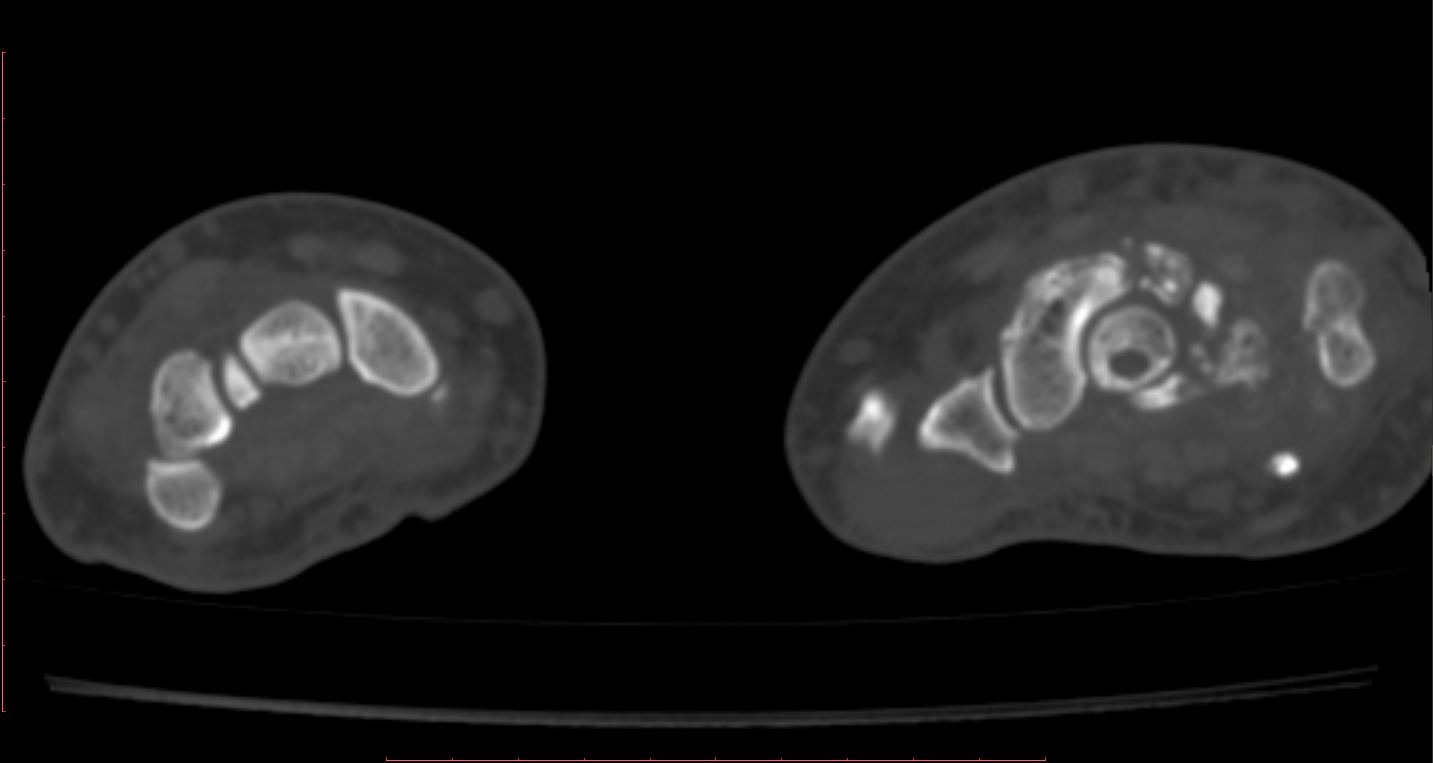

После 6-го коммента добавляю КТ. DICOM тут: http://files.mail.ru/A64E4C объём 14,5 МВ.

К большому моему сожалению, методом КТ не владею. Попробую описать то, что вижу, в надежде, что Вы поправите. Множественные полиоссальные очаги костной деструкции с достаточно четкими контурами (склеротический ободок?), местами с нарушением целостности кортикального слоя. В головчатой кости в деструктивном очаге плотная тень, похожая на секвестр. Полулунная фрагментирована соответственно ас/некрозу. Суставные щели сохранены, хотя соотношения костей запястья в горизонтальной плоскости выглядят не нормально. Мягкие ткани увеличены в обЪеме, дифференцировка структур по ладонной поверхности сохранена, по тыльной поверхности ближе к локтефой четкость теряется, на этом фоне непонятные мне включения. + отмечается расширение сосудистых теней. Остеомиелит и флегмона остаются у меня под большим сомнением. И характерных для нейротрофических нарушений напластований тоже не вижу (возможно, еще не срок?). При РА таких деструктивных изменений не встречала, и остеопороз под ?. Хотелось бы узнать Ваш вариант, уважаемая ЛГ.

Интраоссальные "секвестры" в запятье, а их два, это интраоссальные тофусы. Глыбчатые аморфные образования по плотности больше хряща, но меньше обызвествления, - это тофусы в мягких тканях. Кистовидные изменения костей запястья, с истончением коркового слоя и его частичным прерыванием - характерно для подагры.

Данных за гнойные затёки, абсцессы - нет. Есть инфильтрация клетчатки, объёмное увеличение мягких тканей, признаки синовита (тут МРТ б помогло лучше в плане визуализации).

Фрагментация и выраженное уплотнение полулунной кости - исход болезни Кинбека, с удивительно слабо выраженными признаками ДОА. Пациент не помнит, чтоб в детстве-юности были проблемы с правой кистью... но кто знает, может, у него память избирательная)).